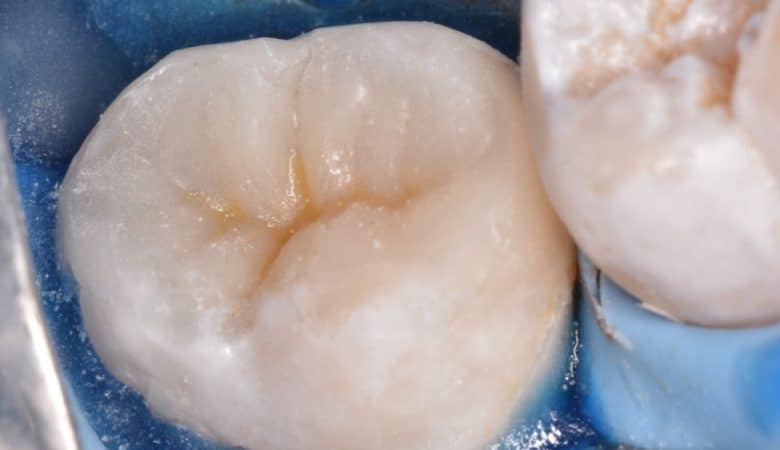

Brand: GC ,Tukoyama

Material: Ever X Posterior

Technique: Composite up technique

In cases of large cavity the choise of the type of restoration mostly go with indirect restoration(crown or onlay overlay ) when there is agreat loss of tooth structure to prevent fracture of the tooth and for long term treatment…